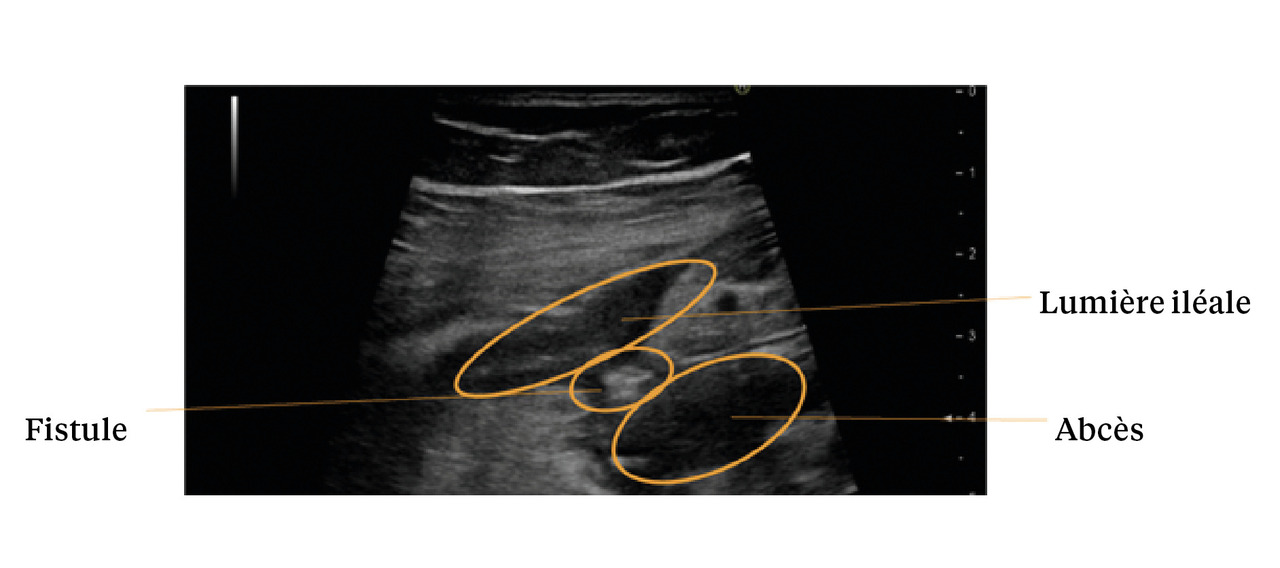

L’échographie permet la visualisation de l’ensemble du cadre colique, de la dernière anse iléale et des anses grêles, par balayage de l’épigastre jusqu’au pelvis. Les points analysés sont l’épaisseur pariétale (fig. 1), le signal doppler, les anomalies de la graisse mésentérique, la stratification pariétale, le péristaltisme, la présence d’ulcérations, d’adénopathies ou de complications (fistule, abcès, sténose ou épanchement intra-abdominal [fig. 2]). L’examen échographique permet de localiser ces éléments sémiologiques et de préciser la longueur de l’atteinte, le cas échéant.3

À l’instar de l’échographie, l’entéro-IRM est une technique d’imagerie validée pour le suivi des sténoses, des fistules et des abcès au cours de la maladie de Crohn grêlique, ainsi que pour l’évaluation de la réponse thérapeutique.1 Ainsi, la concordance entre l’entéro-IRM et l’endoscopie dans la cicatrisation des ulcères de l’iléon terminal est de 90 %, et de 83 % pour l’évaluation de la cicatrisation endoscopique.8 Trois mois après l’introduction d’un nouveau traitement, les scores d’acti­vité en entéro-IRM permettent une évaluation fiable de la réponse thérapeutique, avec des performances comparables à celle des scores d’activité ­endoscopique.8 En revanche, sa faible disponibilité ne permet pas son utilisation pour le diagnostic d’urgence des complications de la maladie de Crohn : d’autres modalités d’imagerie (TDM en particulier) lui sont ici préférées.1